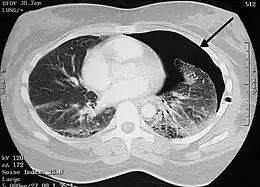

Chest X-ray

A plain chest radiograph, ideally with the X-ray beams being projected from the back (posteroanterior, or "PA"), and during maximal inspiration (holding one's breath), is the most appropriate first investigation.[30] It is not believed that routinely taking images during expiration would confer any benefit.[31] Still, they may be useful in the detection of a pneumothorax when clinical suspicion is high but yet an inspiratory radiograph appears normal.[32] Also, if the PA X-ray does not show a pneumothorax but there is a strong suspicion of one, lateral X-rays (with beams projecting from the side) may be performed, but this is not routine practice.[15][19]

Chest X-ray showing a pneumothorax on the right (left in the image), where the absence of lung markings indicates that there is free air inside the chest

It is not unusual for the mediastinum (the structure between the lungs that contains the heart, great blood vessels, and large airways) to be shifted away from the affected lung due to the pressure differences. This is not equivalent to a tension pneumothorax, which is determined mainly by the constellation of symptoms, hypoxia, and shock.[13]

The size of the pneumothorax (i.e. the volume of air in the pleural space) can be determined with a reasonable degree of accuracy by measuring the distance between the chest wall and the lung. This is relevant to treatment, as smaller pneumothoraces may be managed differently. An air rim of 2 cm means that the pneumothorax occupies about 50% of the hemithorax.[15] British professional guidelines have traditionally stated that the measurement should be performed at the level of the hilum (where blood vessels and airways enter the lung) with 2 cm as the cutoff,[15] while American guidelines state that the measurement should be done at the apex (top) of the lung with 3 cm differentiating between a "small" and a "large" pneumothorax.[33] The latter method may overestimate the size of a pneumothorax if it is located mainly at the apex, which is a common occurrence.[15] The various methods correlate poorly but are the best easily available ways of estimating pneumothorax size.[15][19] CT scanning (see below) can provide a more accurate determination of the size of the pneumothorax, but its routine use in this setting is not recommended.[33]

Not all pneumothoraces are uniform; some only form a pocket of air in a particular place in the chest.[15] Small amounts of fluid may be noted on the chest X-ray (hydropneumothorax); this may be blood (hemopneumothorax).[13] In some cases, the only significant abnormality may be the "deep sulcus sign", in which the normally small space between the chest wall and the diaphragm appears enlarged due to the abnormal presence of fluid.[16]